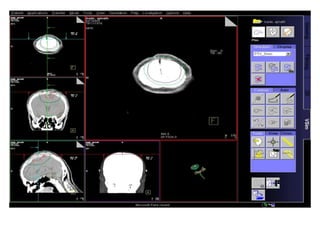

Robotic Radiosurgery

Highly precise RT delivery system

- Respiratory tracking

- Fiducial based tracking system

- Intra-fraction motion correction

- Uncomparable dose distribution

- X-ray based image verification

Hypofractionated RT

- High dose short course RT

- Higher BED delivered to target